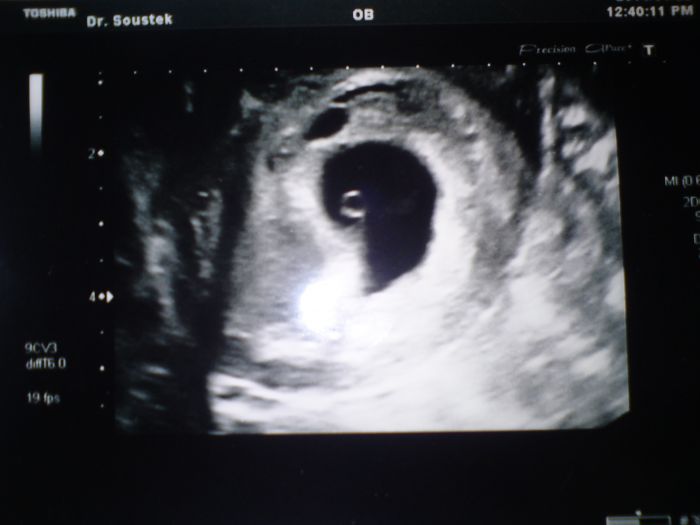

ahoj holky ja beru jen klasickou listovku.. na genetice zjistili, ze se mi dobre vstrebava a magnesko.. ja mam celej zivot krece v lytkach z nedostatku horciku a ted to bylo nejak horsi tak mi ho dr napsal... a upravila jsem si stravu a diky tomu ma dnes o 2kg mene.. jinak kontrola na 1* uz bylo srdicko jako silene a uz jsem dostala i prukazku. vyfasovala jsem fotku ale neni na ni skoro nic videt jen zloutkovy vacek, ale i tak je to fajn